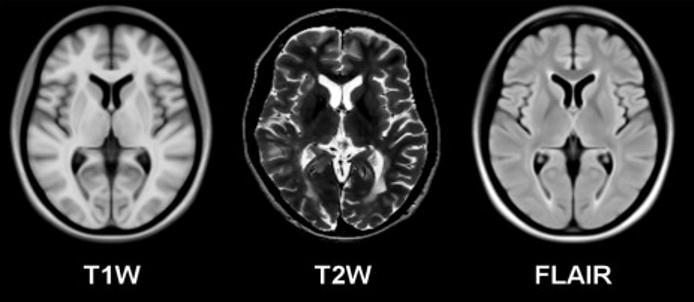

The initial image data consisted of random MRI images belonging to multiple categories. It included the spine, bladder, and brain.Thebrainimagescorrespondedtothreesub parts,namelyT1W,T2W,andflair.ThemajorityportionofT1Wimagesis bright with dark ventricles. The T2W is dark with bright ventricles, whilethe flair has a slightly bright greyish portion with dark ventricles. The classification of a particular category needs at least one other differentiation against it. The image data had around 720 images of the brain (T1W, T2W, Flair), spine, gall bladder. The number of samples from each category was unknown. The classification needed T1W, T2W, and flair images from the two categories (ABNORMAL and NORMAL). The dataset had 400 images with an unknown number of samples from each class. MRI: an imaging technique that uses magnets(magneticfield)andradiowavestocreateimagesofinnerpartsofthebody.ACTusesX raystodothesamefunction.

Fig.3 MagneticResonanceImageofthebrain